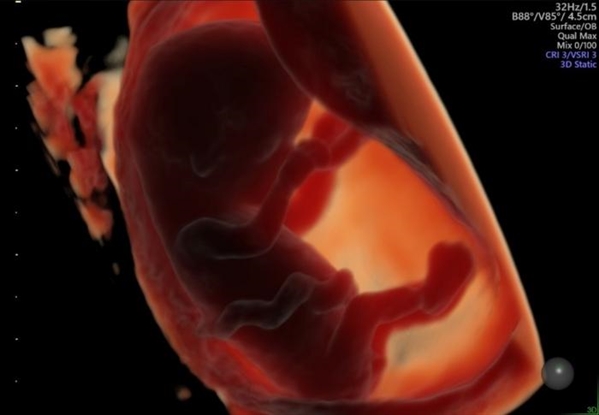

通过3D宫腔超声检查获得的一枚约11周的胚胎影像。图片来源:Generation R study group

研究人员在孕7周、9周和11周时,通过经阴道超声测量胚胎的头臀长(CRL)及卵黄囊体积。

论文第一作者、伊拉斯姆斯大学医学中心的Celine Lin表示:“我们观察到,女性摄入超加工食品与不孕风险、备孕时长并未呈现一致关联,但与孕7周时胚胎生长略缓、卵黄囊偏小有关。早期发育差异虽小,但在科研和人群层面意义重大。这是我们首次证实,超加工食品不仅关乎母亲健康,还可能与后代发育相关。”

已有其他研究证实,孕早期胚胎生长迟缓与不良分娩结局风险升高相关,包括早产、低出生体重,以及儿童期心血管疾病风险上升。卵黄囊发育异常则与流产、早产风险增加有关。